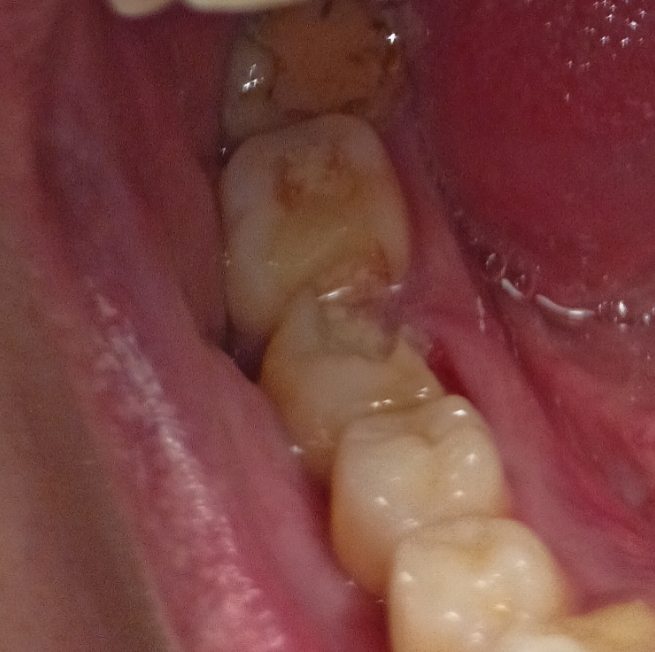

2323.jpg 238Кб, 1412x2047

1412x2047

Аноны, добрый вечер.

Посоветуйте пасту зубную после пломбирования и чистки от камня передних зубов.

Спасибо.

Аноним 06/08/25 Срд 05:38:29 1634925 25

Ска, весь рот в гное, будто бы стоматит, сходил к зубным феям - сказали все збс с корнями зубов и ни одного намёка на кариес где-либо, хотя начиналось всё будто бы флюс и самый пиздец около одного зуба, прописали онли антибиотики, но самое очко , что болезненность ещё и в области мягких тканей подбородка, который и отдает в этот самый пиздец при надавливании - даже будто бы второй подбородок чуть-чуть присутствует, температура и общая слабость, есть риск флегмоны? пиздец за шо(

Аноним 06/08/25 Срд 10:08:53 1634947 26

Как профиль лица меняется после удаления восьмерок? В инете нашел только фотки до/после у женщин, и вроде как челюга уменьшается. У мужиков так же? После удаления не получится больше моггать челюхой омежек?

Аноним 07/08/25 Чтв 13:36:06 1635134 27

>>1634947

>Как профиль лица меняется после удаления восьмерок